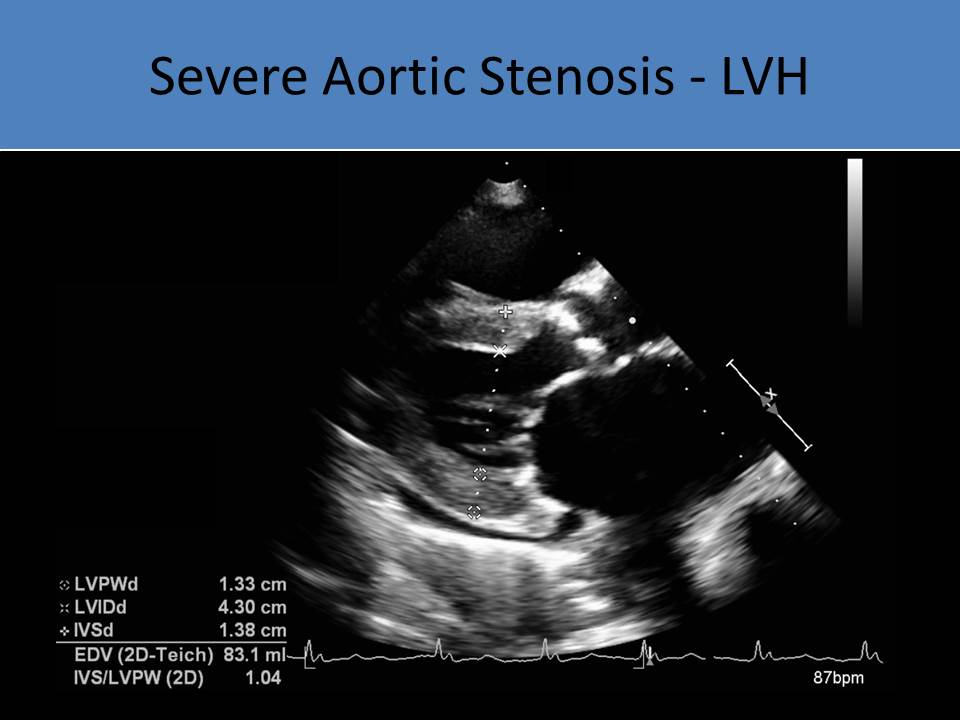

• LVH noted on LV m-mode due to pressure overload

• LVH will be concentric (hypertrophic cardiomyopathy= asymmetric LVH)

Secondary Findings:

• Left ventricular hypertrophy with left heart pressure overload

• Increased LV mass

LVH M-modeSevere Aortic Stenosis - LVH